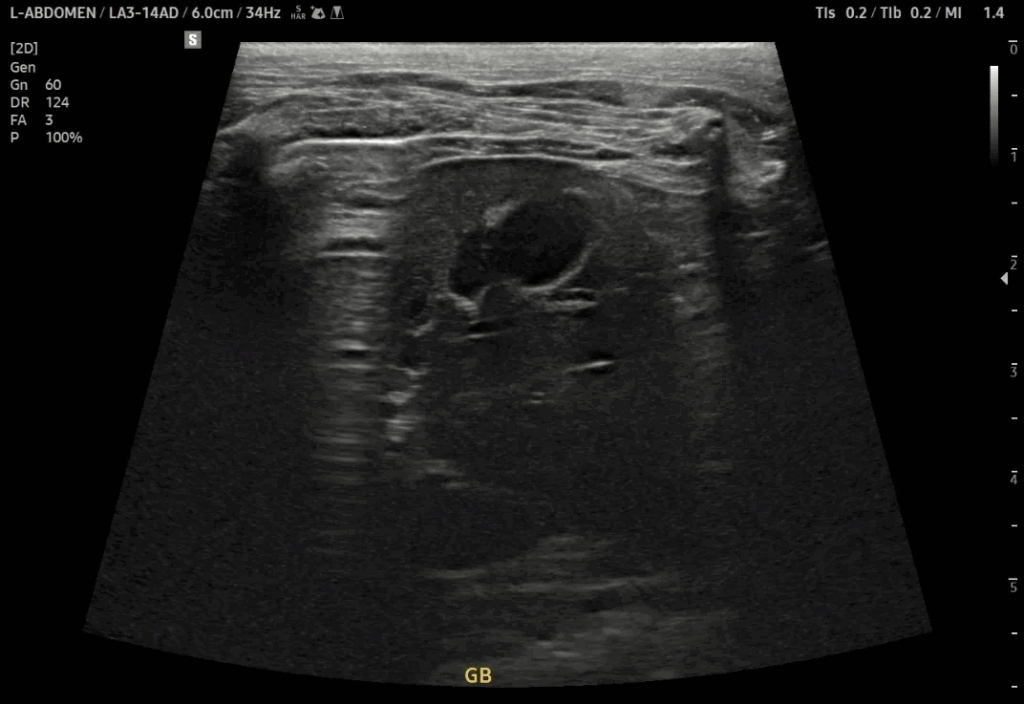

강아지가 갑자기 턱 밑이 부풀거나, 한쪽 얼굴이 비대칭으로 보이는 증상이 나타나면 단순한 림프절염이나 종양으로 오해하기 쉽지만, 침샘낭종(Sialocele)이라는 비교적 흔한 질환일 수 있습니다. 오늘은 턱 밑 멍울과 통증을 증상으로 내원한 3살 강아지의 사례를 통해, 침샘낭종의 진단과 치료 과정을 자세히 소개드리겠습니다. 강아지 침샘낭종 치료 케이스 이번 환자는 3살의 중성화한 암컷 강아지로 보호자님께서는 내원 당일 “우측 턱 밑에 […]